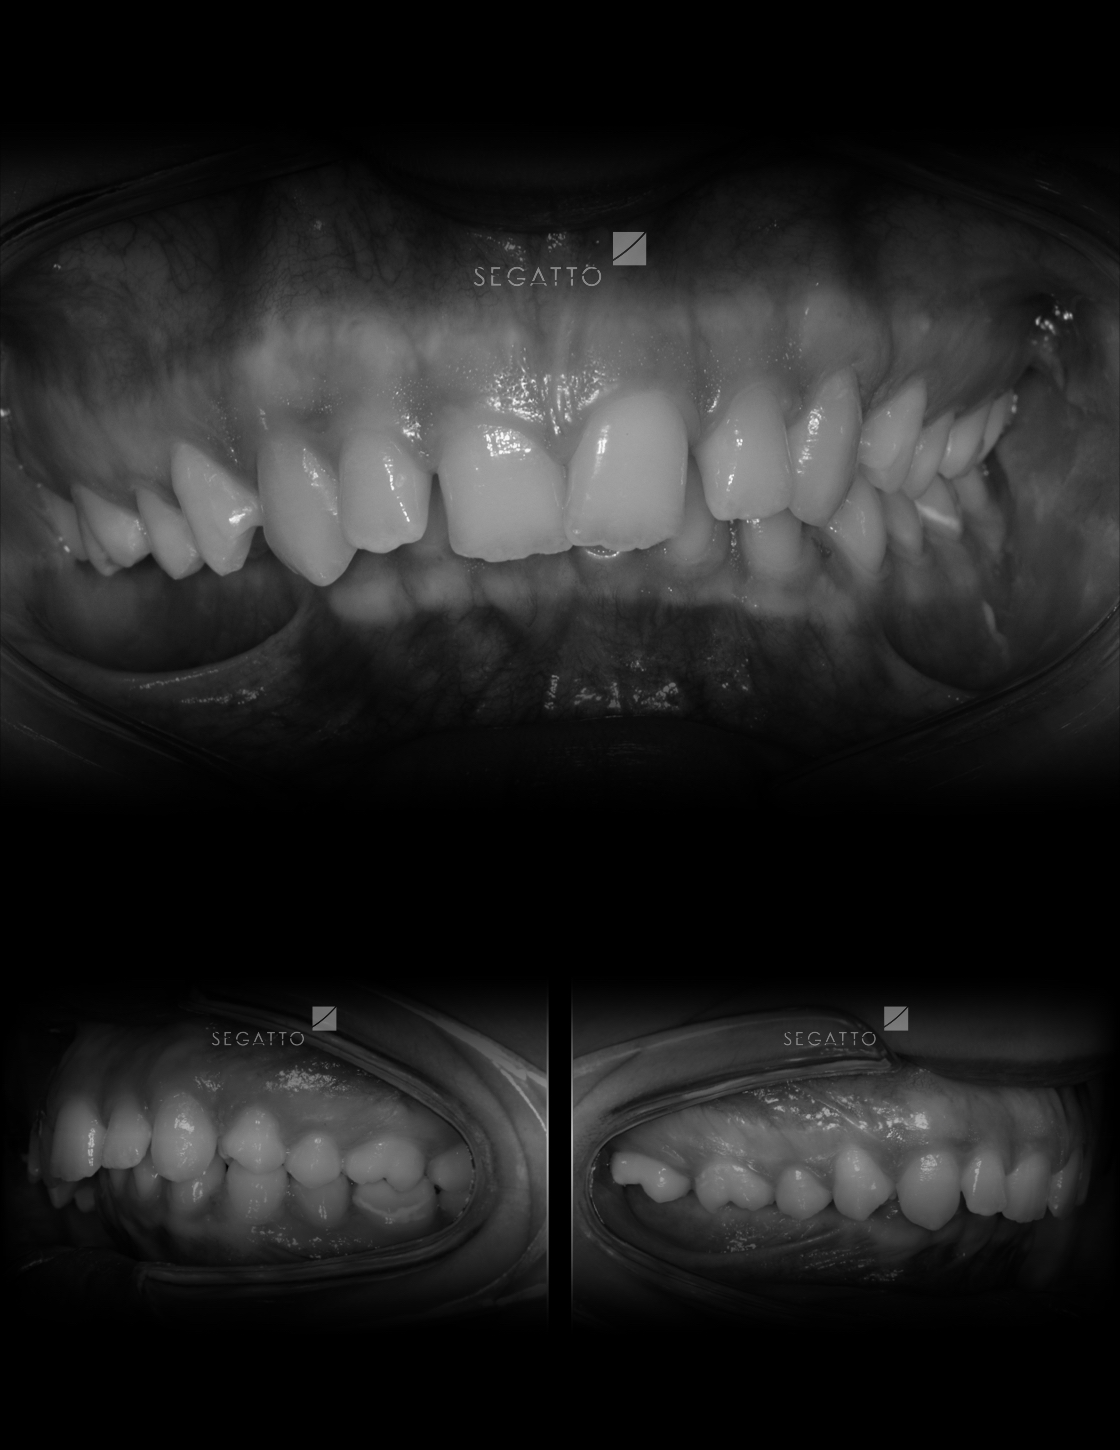

Orthodontics

Cases